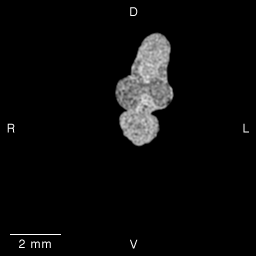

Stage 14 (Day 32), transverse slice 12